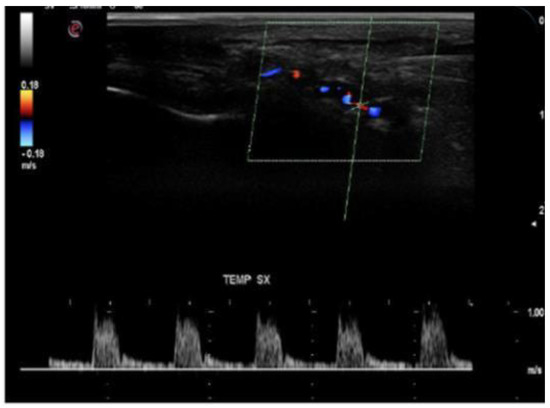

- In the acute phase of unilateral clinical eye involvement, absent (undetectable) signals in the homolateral PCAs (not corresponding to homolateral internal carotid artery occlusive disease) are classified as Doppler US features in acute arteritic AION (consecutive to GCA). In addition, we can identify a high resistance index (RI), with decreased velocities (especially EDV) in all retrobulbar vessels, in both orbits [9,10,11,12,13,14,15,60,61,62] (Table 2) [13].

- GCA acute cases with no evident clinical ocular involvement present a decrease in arterial flow in bilateral orbits, with increased RI, and diminished velocities (especially EDV). The severely diminished flow in the PCA, associated with diminished flow in the CRA and very high flow in the OA (all on the affected side) are the common US features in this type of patient. This US aspect is an essential predictor of an imminent A-AION and needs prompt treatment with high-dose corticosteroids [9,10,11,12,13,14,15,60,61,62] (Figure 7) [11].